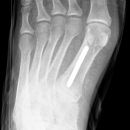

Metatarsale 5

Lisfranc Luxationsfraktur